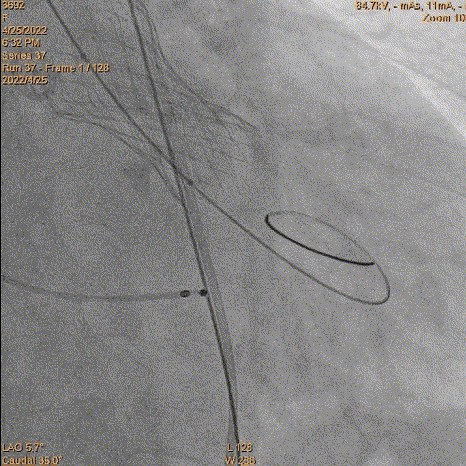

对侧上圈套器准备

4、跨瓣:瓣膜跨瓣出现困难,计划使用圈套器。由于没有22F大鞘,内连鞘无法拆卸,选择左侧穿刺导入导管。右侧双导丝,送入Lunderquist,心室较大。扩张后,血压较稳定。经尝试无法退球囊,撤出系统。通过对侧使用抓捕器,将导丝全撤,导入AL1.0导管重新跨瓣。鉴于左侧入路有角度,使用泥鳅导丝带上导管,做圈套器。顺利抓住J型导丝,抓捕器顺利抓捕瓣膜过瓣。

重新过瓣

瓣膜过瓣